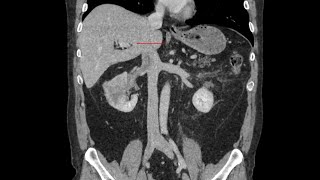

Лапароскопическая нефрэктомия справа, тромбэктомия из НПВ

Место: ФМБЦ Операция: Лапароскопическая нефрэктомия справа, тромбэктомия из НПВ Бригада: Галлямов Э.А. Сергеев ...

АНО МВС